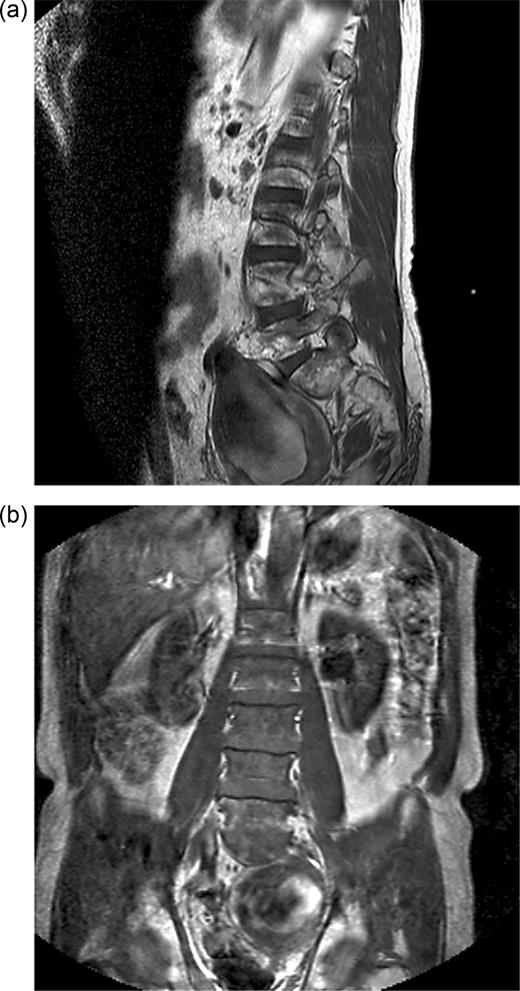

Orthopaedic review detected sensory loss in the S1 dermatome and foot drop on the left side. He was clinically well. Urgent magnetic resonance imaging (MRI) demonstrated a 9 cm left iliac aneurysm in contact with the left L5 nerve root and in close proximity to the S1 nerve root (Figure 1a and b). There was also left ureteric dilatation with hydronephrosis. The spinal cord was normal.

(a) T1-weighted sagittal MRI showing internal iliac aneurysm. (b) T1-weighted coronal MRI showing internal iliac aneurysm.